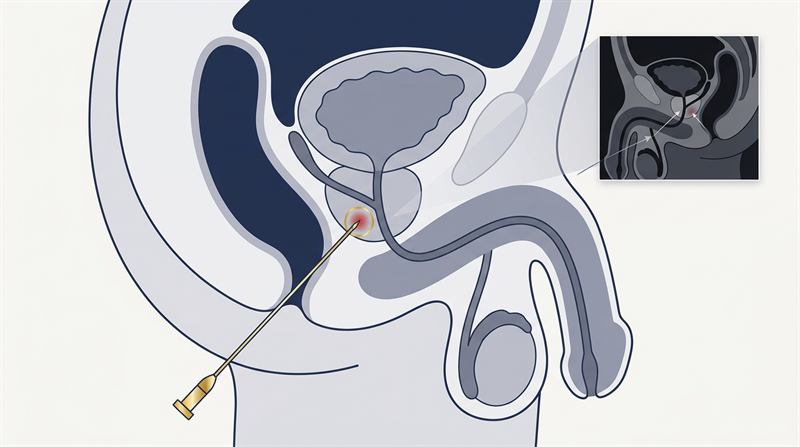

Dr Raji Kooner successfully completed the first pure single port robotic procedure in NSW — a true single-incision approach without any assisting ports — with support from Dr Ryan Nelson (USA).